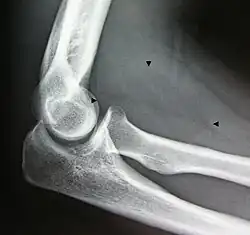

Bone formation may be seen in both lipomas[26] and liposarcomas (a well-differentiated one pictured).